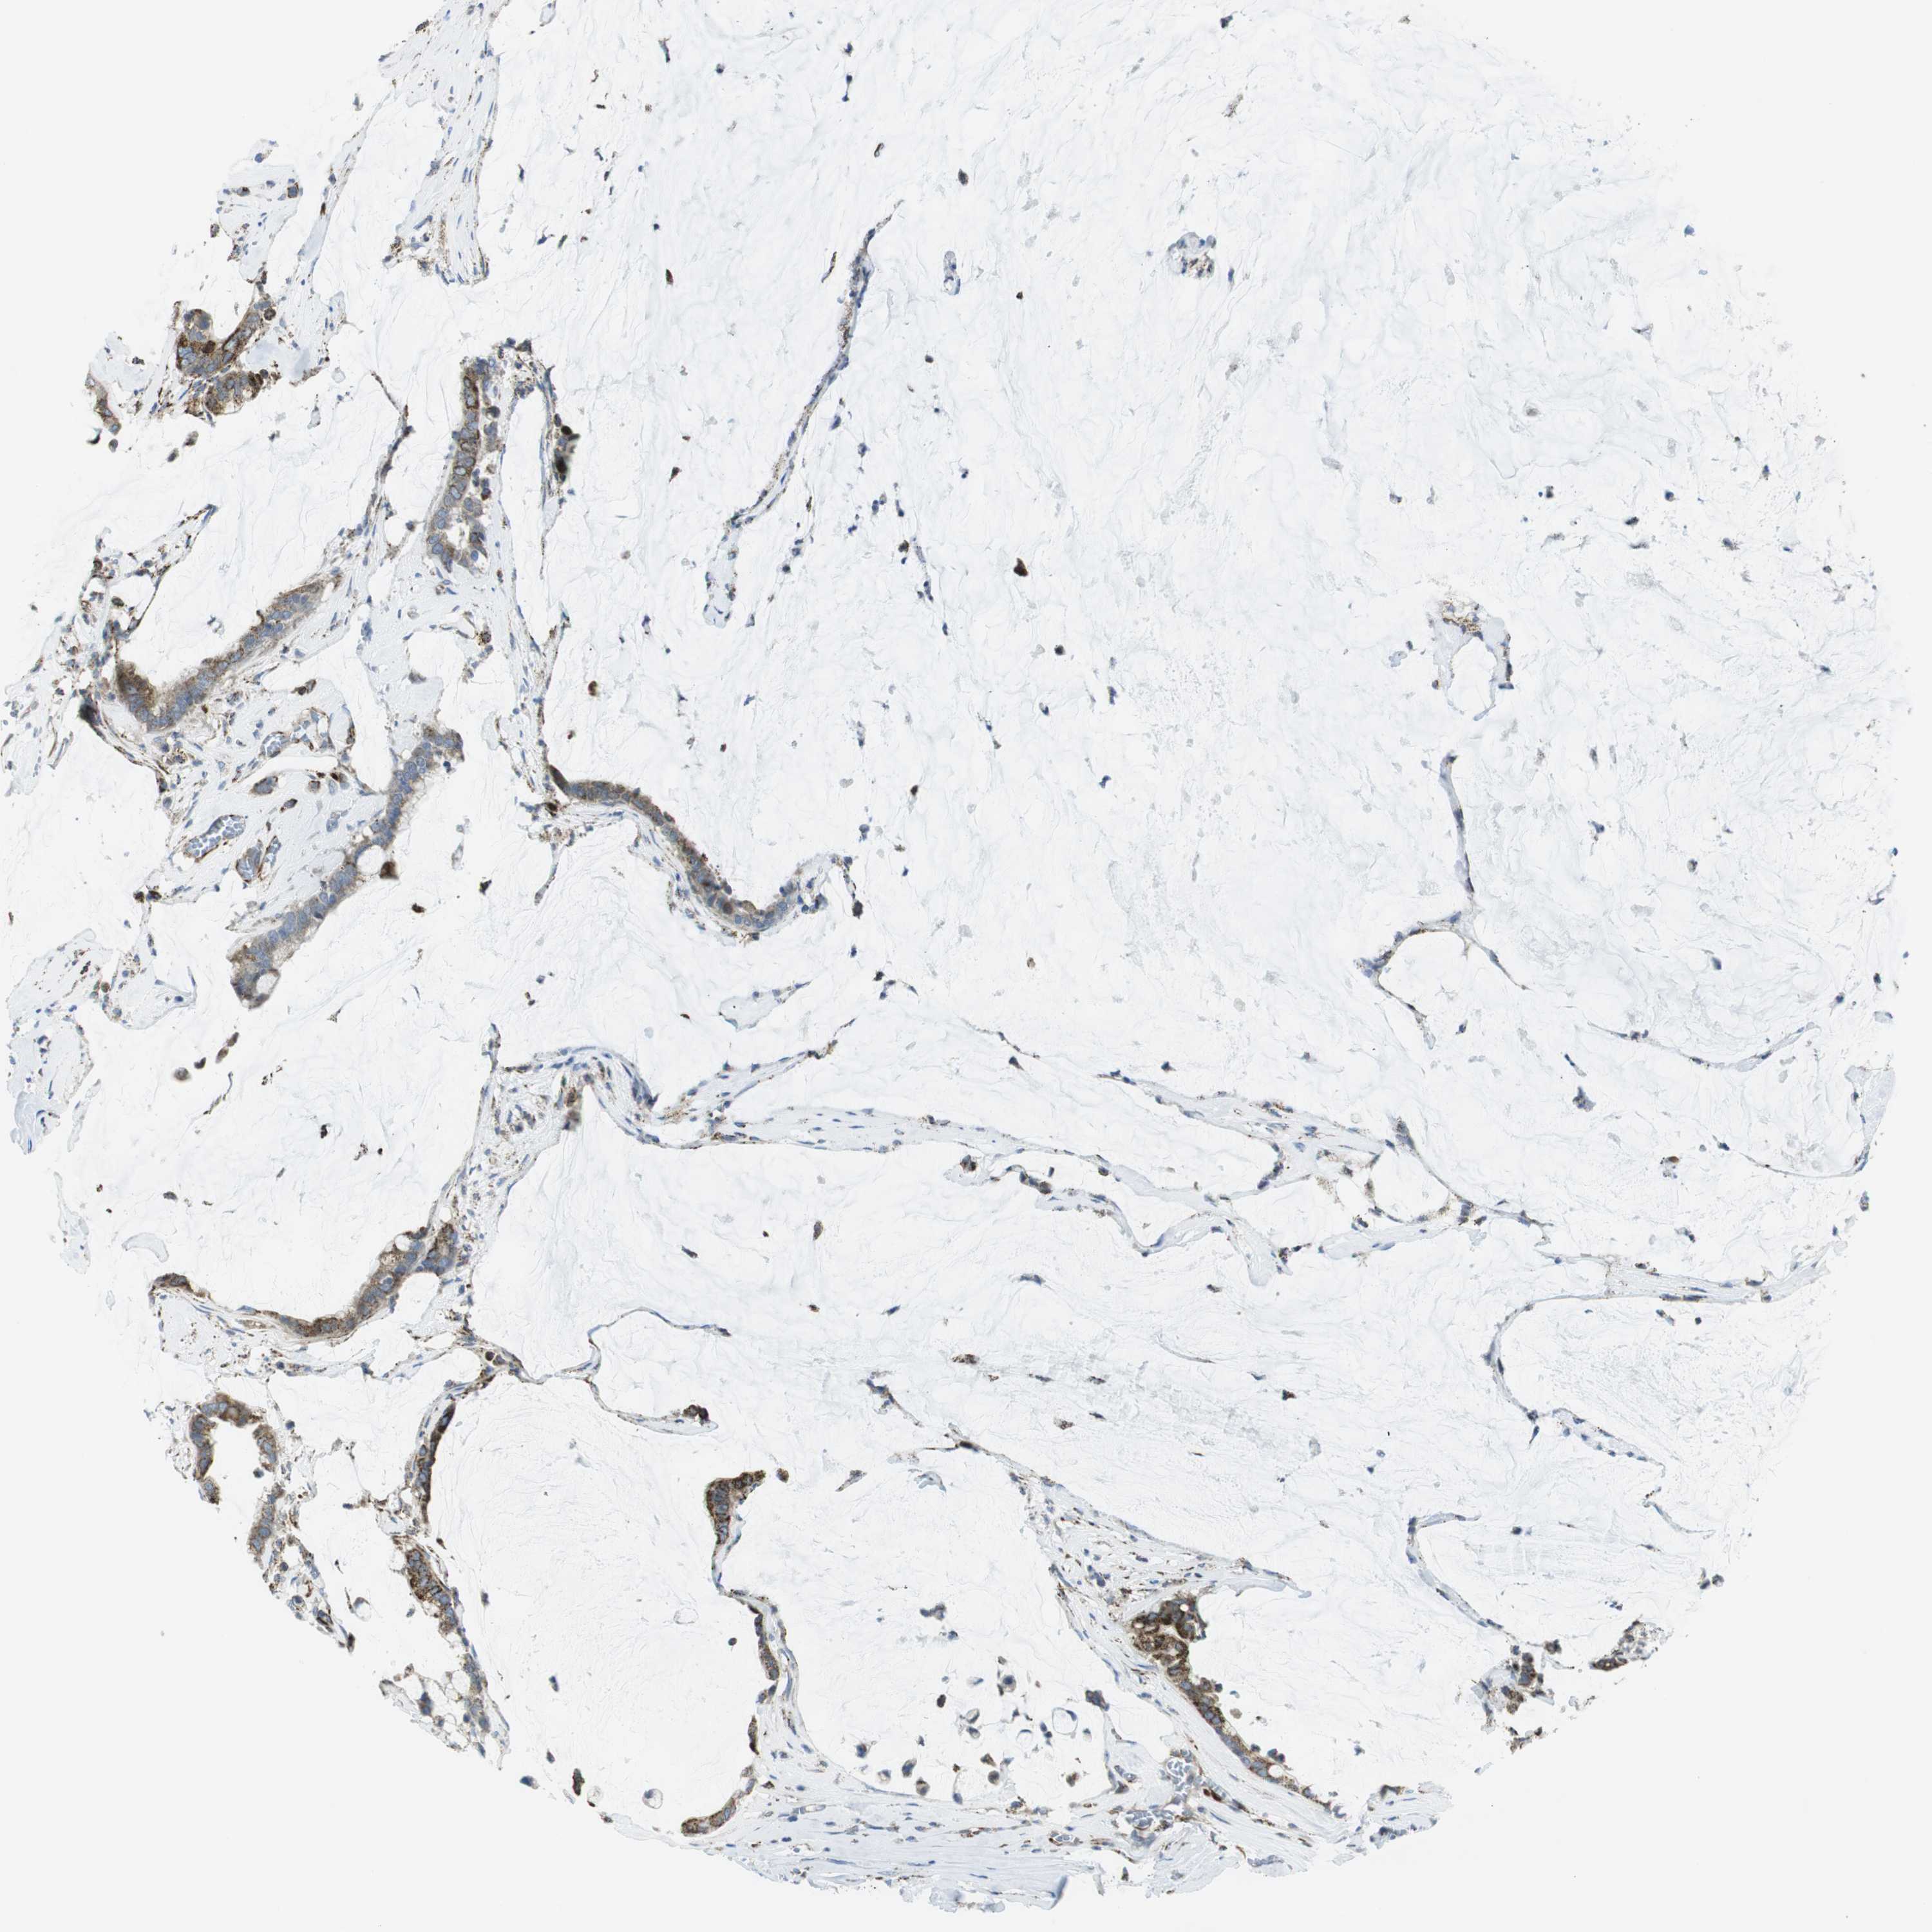

PANCREATIC CANCER - Protein expressioni

A mouse-over function shows sample information and annotation data. Click on an image to view it in a full screen mode. Samples can be filtered based on level of antibody staining by selecting one or several of the following categories: high, medium, low and not detected. The assay and annotation is described here.

Note that samples used for immunohistochemistry by the Human Protein Atlas do not correspond to samples in the TCGA dataset.

Antibody stainingi

Antibody staining in the annotated cell types in the current human tissue is reported as not detected, low, medium, or high, based on conventional immunohistochemistry profiling in selected tissues. This score is based on the combination of the staining intensity and fraction of stained cells.

Each image is clickable and will lead to virtual microscopy that enables deeper exploration of all samples and also displays staining intensity scores, fraction scores and subcellular localization as well as patient and tissue information for each sample.

Antibody HPA014849

Staining

High

Medium

Low

Not detected

Intensity

Strong

Moderate

Weak

Negative

Quantity

>75%

75%-25%

<25%

None

Location

Nuclear

Cytoplasmic/membranous

Cytoplasmic/membranous,nuclear

Adenocarcinoma, NOS